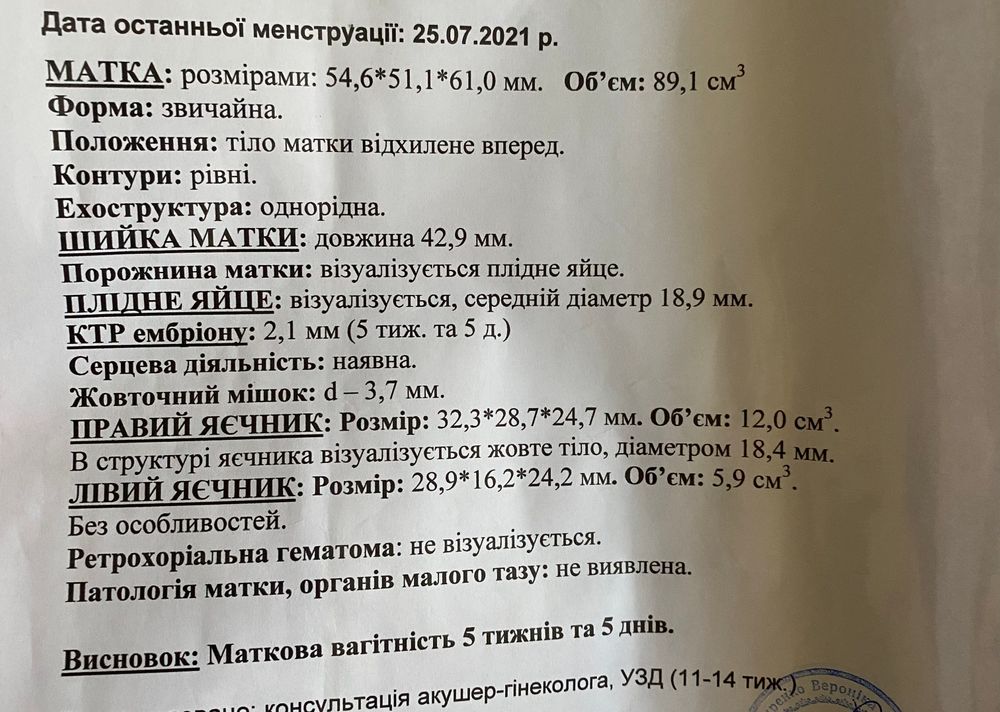

MariDav, мы с вами рядышком идём, у меня сегодня тоже первое УЗИ, срок по М 5 недель 5 дней, а по УЗИ 6 недель. Нашли ПЯ и ЖМ. Эмбриончика пока не видно, но я верю, что все хорошо будет🙏